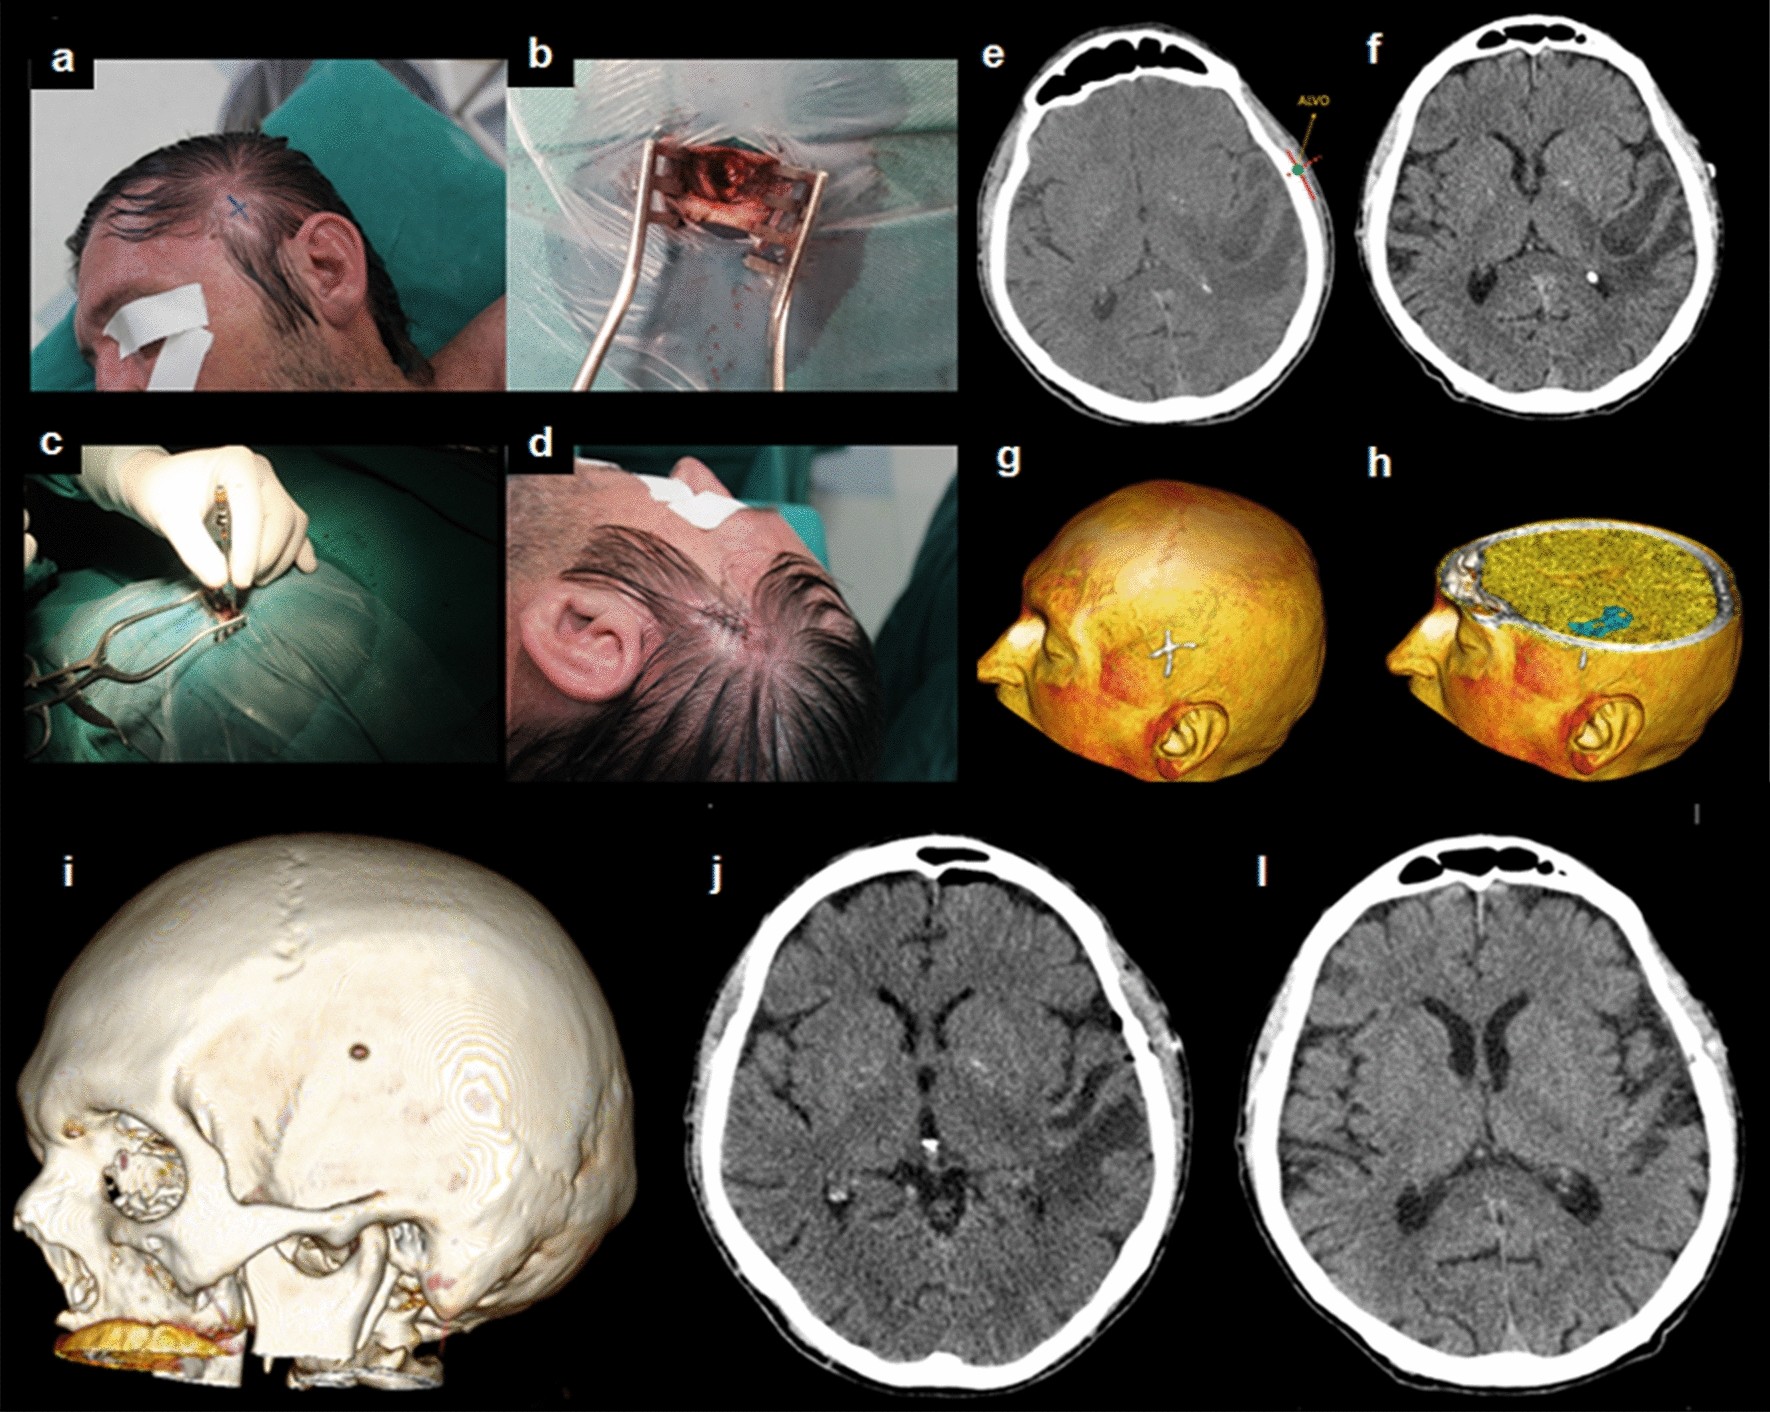

Figure 4

From: Minimally invasive supratentorial neurosurgical approaches guided by Smartphone app and compass

A 58-year-old man with a diagnostic hypothesis of left temporal brain abscess submitted to drainage through trepanation. (a), (b), (c), and (d) Intraoperative images showing the surgery step-by-step; (e) Surgical planning (f) Cranial CT scan after targeting; (g) and (h) pre-operative three-dimensional virtual reality reconstruction (3DVR) showing the target and its relationship with the lesion; (i) postoperative 3DVR with the trepanation; (j) Immediate postoperative cranial CT scan; (l) late radiological control, after 6 weeks, with complete resolution of the abscess.